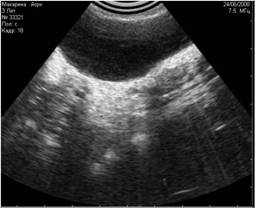

- сетевые - вызванные включёнием одновременно с УЗИ-аппаратом электрических приборов и сотовым телефоном (Рис.1; 2);

Рис1. Помехи, вызванные включённым рядом с аппаратом УЗИ сотовым телефоном. Во избежание этого лучше просить владельца выключать сотовый телефон при проведении ультразвукового исследования. |

Рис2. Помехи, вызванные работающими электроприборами, включёнными в сеть рядом с аппаратом УЗИ. |